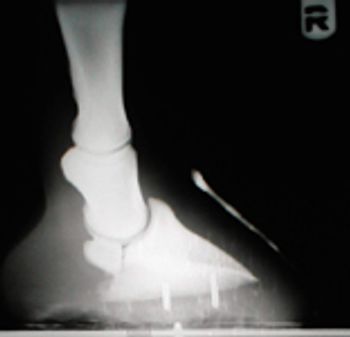

The advantage of contrast studies is that they highlight and allow assessment of the tissue-contrast interface, and allow assessment of the size, shape, location and patency of various viscera. Contrast can be used to locate structures not apparent on survey films, such as masses, obstructions, and foreign object.